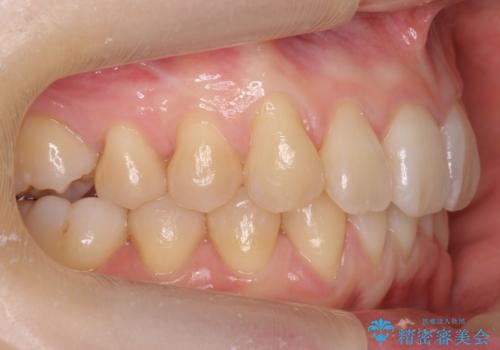

- 前歯のがたつきを主訴に来院。

下の前歯は生まれつき1本少ない状態でした。

左上の犬歯が入りきらずねじれており、かみ合わせもずれていました。

左上の小臼歯を1本抜いて治療しています。

前歯は内側に傾いており(ラビッティング)、過蓋咬合(深いかみ合わせ)を呈していました。

難しい治療でしたが綺麗に咬み合わせることができ、また前歯もしっかり当たるように治療できました。